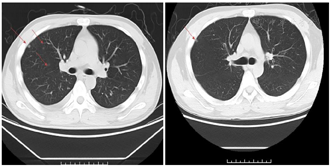

正规治疗前CT显示两肺多发小结节,大者约11mm,位于右肺中叶胸膜下。治疗1个月后,两肺只见少量小结节影,较大的约4mm(图9)。目前随访时间16个月,腹腔肿大淋巴结消退,双肺结节病灶明显减少缩小,病情平稳。